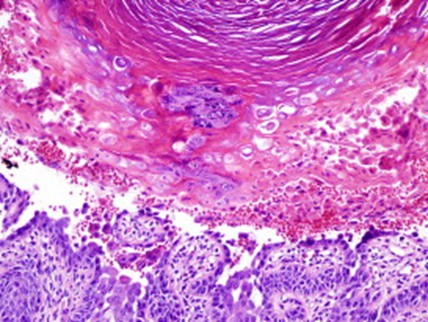

The prevalence of DD is estimated to be between one in 30,000 and one in 100,000. The disorder usually manifests in the first or second decade, presenting with variable expressivity as hyperkeratotic, greasy papules in a seborrheic distribution. Lesions may become verrucous, fissured, and secondarily infected. Nail changes include V-nicking and erythronychia. The oral mucosa is involved in 50% of patients. Blepharitis and dry eyes may be observed. Some patients may display neurologic abnormalities (intellectual impairment, seizures, and depression). Segmental DD is due to mosaicism. Histologically, DD is characterized by focal acantholytic dyskeratosis (suprabasal clefts, corps ronds and grains). (1,2)

Histologic image of Darier disease for DWII

Image from JAAD 2008 (2 Suppl 1): S50-1.